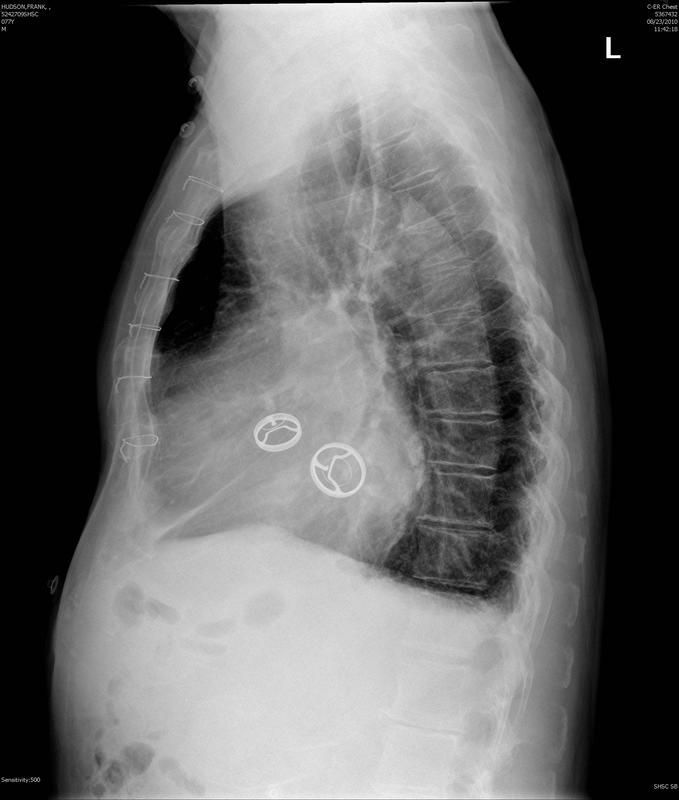

prosthetic valves lat